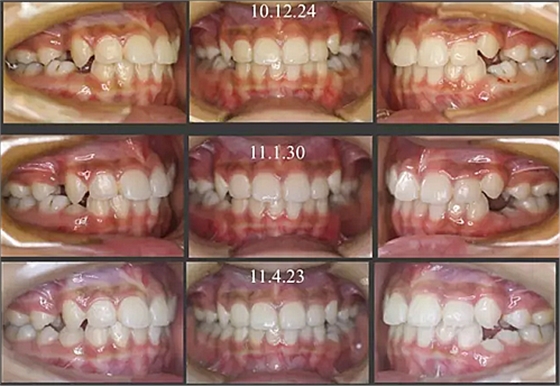

經(jīng)過三年零九個(gè)月的看護(hù),最終戴上了固定矯治器,但是大家不難發(fā)現(xiàn),孩子的牙齒已經(jīng)排齊,上下中線也基本對齊,面型也好看多了,這樣矯正就變得簡單,療程自然縮短,孩子也不遭罪了。

這個(gè)故事告訴我們,只有家長早點(diǎn)把孩子帶給正畸醫(yī)生檢查,才能早期發(fā)現(xiàn)早期治療。起到了事半功倍的效果。矯正以后還不容易復(fù)發(fā),因?yàn)閺?8年的初診到11年戴矯正器這三年多的時(shí)間里,孩子的牙齒是自己長好的。